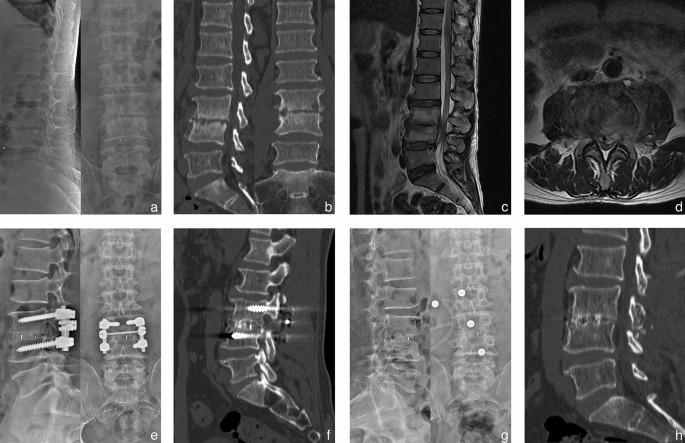

The average lordosis angles of groups A and B at the TMP increased to 28.0° ± 1.8° and 27.8° ± 2.0°, respectively from 16.1° ± 2.0° and 17.2° ± 1.6°, respectively. At the FFU, the correction was not lost, and the lordosis angle of the two groups was 28.6° ± 2.1° and 28.5° ± 1.8°, respectively, which significantly improved in comparison with the preoperative measurements. The mean time of bone graft fusion was 7.6 ± 0.8 and 7.3 ± 0.8 months in group A and B respectively (P > 0.05) (Figs. 1 and 2).

A 53-year-old male shepherd diagnosed with L3-4 brucella spondylitis underwent one-stage posterior interbody fusion and debridement procedure. Preoperative X-ray revealed intervertebral height loss and significant narrowing of the affected disc space. Preoperative CT and MRI scans exhibited erosions of the superior and inferior endplates, along with evidence of nerve compression. (a–d) Postoperative X-ray and CT images demonstrated satisfactory positioning of the internal fixation and cage. (e–f) The final follow-up conducted at 26 months indicated successful bone fusion following the removal of instrumentation, as evidenced by radiographic and CT examinations (g–h).